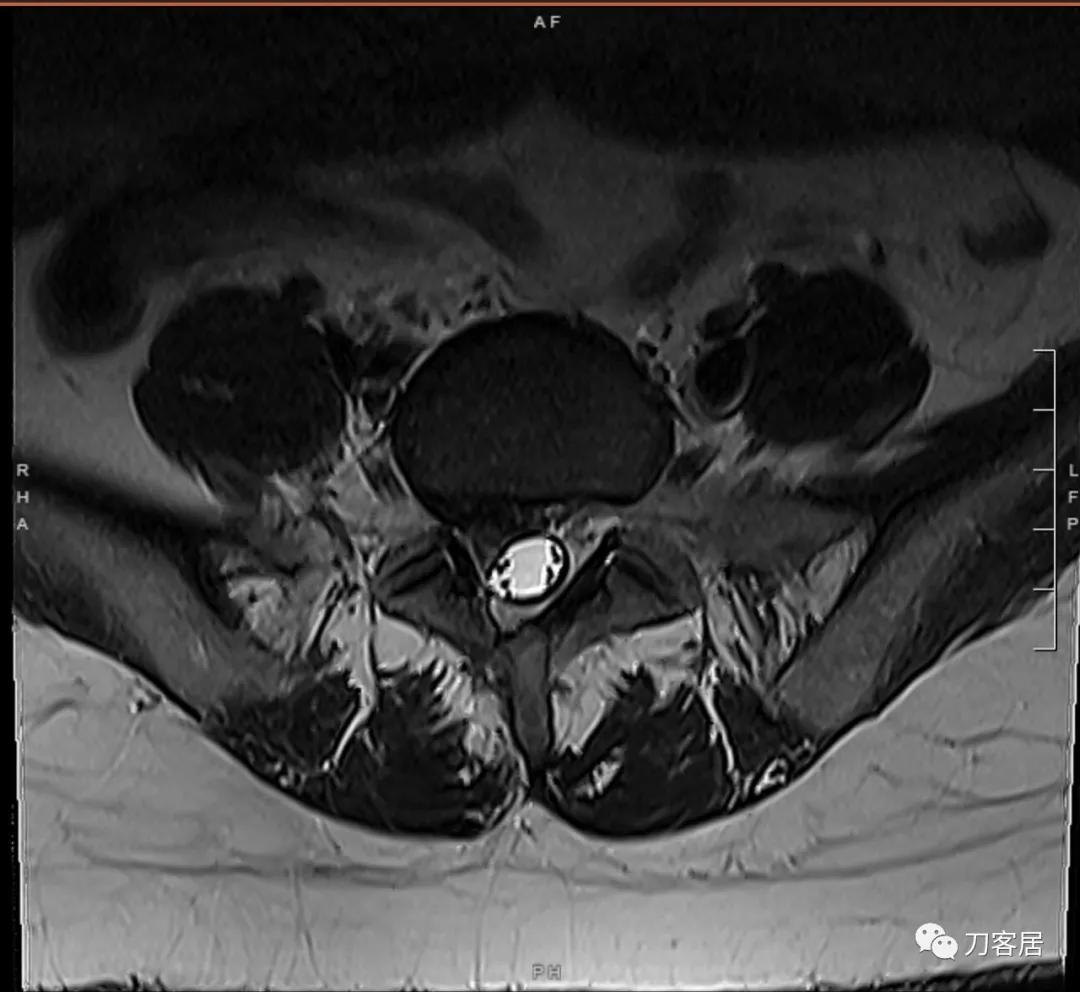

以下是患者的影像资料:

图3. 微创术前腰椎MRI横截面,提示腰5骶1椎间盘突出,右旁侧型,较大。右侧椎板似乎有缺损,应该是原来做过手术,减压所致的骨缺损。